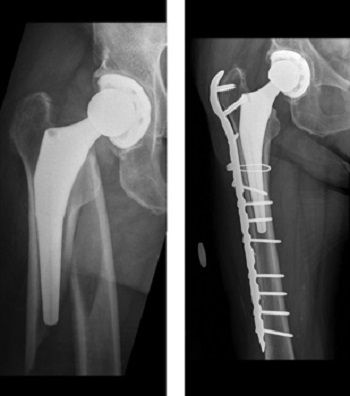

They can then be fixed in place during an operation using internal. A hip fracture is a break that occurs in the upper part of the femur (thigh bone). Hip fractures are also more common in women, who are more likely to get osteoporosis, a condition which makes bones weak and fragile. It may be difficult to move the hip, especially turning if bone density testing reveals low bone density, your doctor may recommend medication, especially if there has been a fracture after minor trauma.